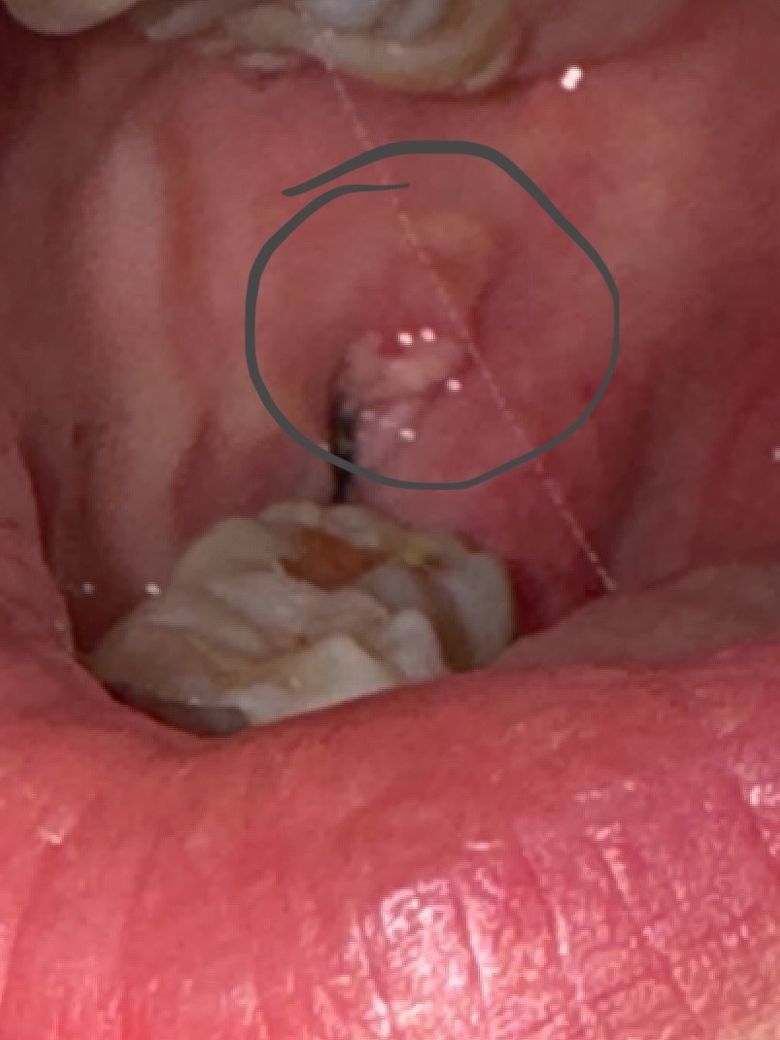

2번 사진이 현재요ㅠㅠ

사랑니 자리와 무관하게 하얀게 생겼어요

문제있는걸까요?? 답변 주시면 감사하겠슺니다.....

• 2번 째 사진

발치 부위 주변으로 다소간 염증 상태인 것 같습니다. 보통 통증은 발치 후 1~2주까지도 있을 수 있습니다. 통증 없다가도 생기기도 하고요. 일단 처방된 약 잘 복용하세요

고생하셨습니다 사랑니 발치 후 잇몸이 자라나는 과정입니다 정상 적인 치유 과정으로 보입니다 사랑니 발치 후 주의사항을 지켜주세요 1달에서 길면 2달 정도 지나야 그 부분 불편감이 없으 실수 있습니다 통증이 있으시면 치과에서 준 처방약이 남았다면 드시고 없으시면 약국에서 파는 진통제 일단 드시고 내일 치과에 내원하시길 바랍니다

사랑니 뽑은 부위 뒤쪽이 자극이 가면 염증 반응이 나타난 후 가라앉기 시작하면 하얀색의 잇몸 딱지 앉은 것입니다. 그냥 두면 뽑은자리 아물면서 저절로 같이 아물게 됩니다.